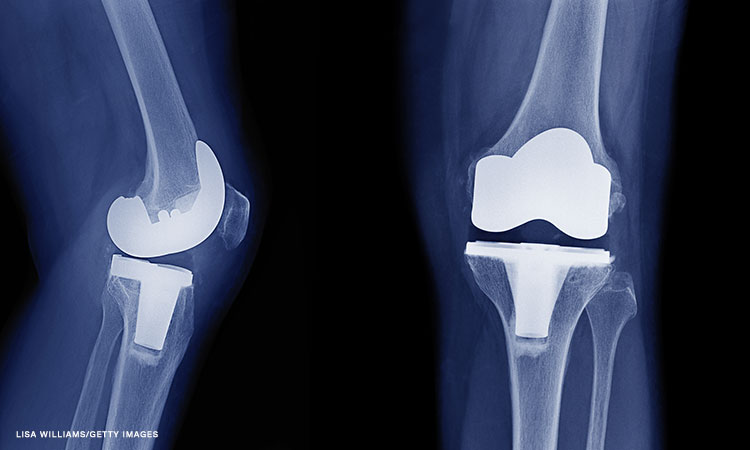

In addition, the measurement looks at the severity of the osteoarthritis on X-rays — “if it’s bone on bone” — as well as how many parts of the knee are affected: the femur (thigh bone), tibia (shin bone), and patella (kneecap).